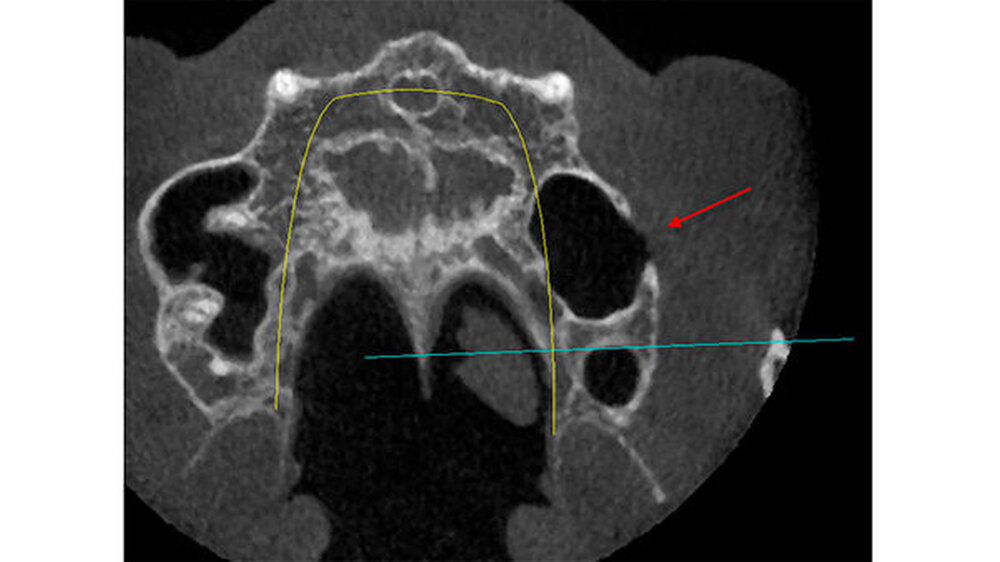

Die vor der geplanten Implantation gesichtete DVT hatte zunächst keinen knöchernen Defekt ausgewiesen. Erst bei nochmaligem und kompletten "Durchscrollen" aller Aufnahmen wurde der Defekt sichtbar (Abbildungen 2 bis 5).